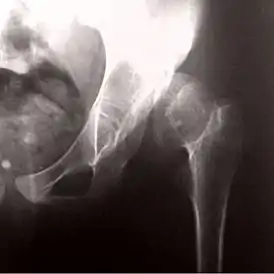

![]() Рентгенограмма, демонстрирующая развитие псевдоартроза при врожденном вывихе бедра | |

Врожденный вывих бедра также может стать причиной возникновения псевдоартроза.

Диагноз ставится на основании рентгеновских снимков в двух взаимно перпендикулярных проекциях и клинических проявлений.